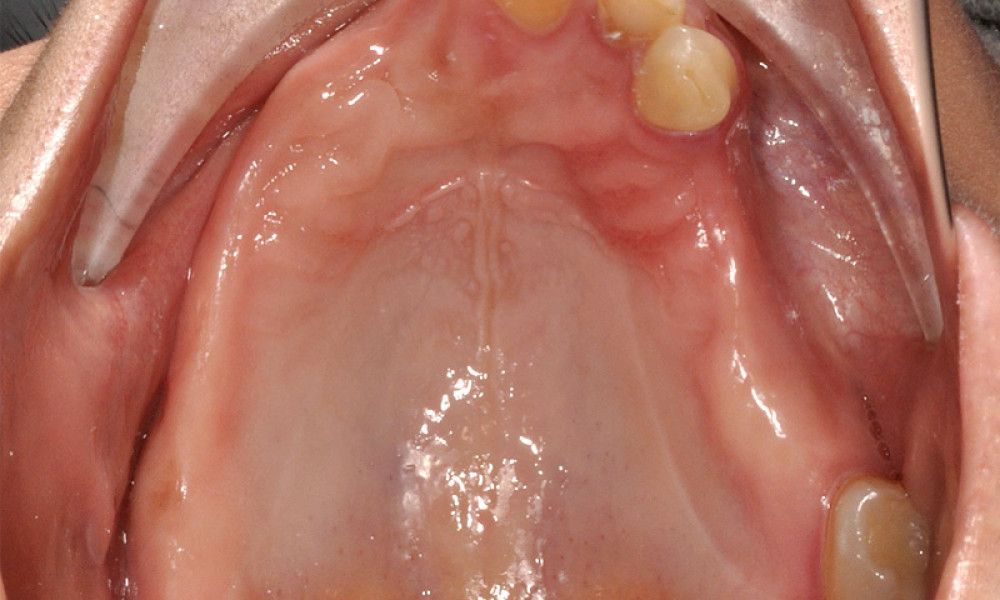

Los Implantes de Carga Inmediata son una solución práctica y definitiva para el desdentado total, es un tratamiento el cual una vez que se opera y se colocan los implantes, por un periodo entre 24 horas a 48 horas, se colocan los dientes en forma provisional, de esta forma el paciente queda con algo fijo mientras el implante se adhiere al hueso. Su principal ventaja radica en la reducción o eliminación del tiempo de espera entre la colocación del implante dental y la colocación de los dientes fijos.